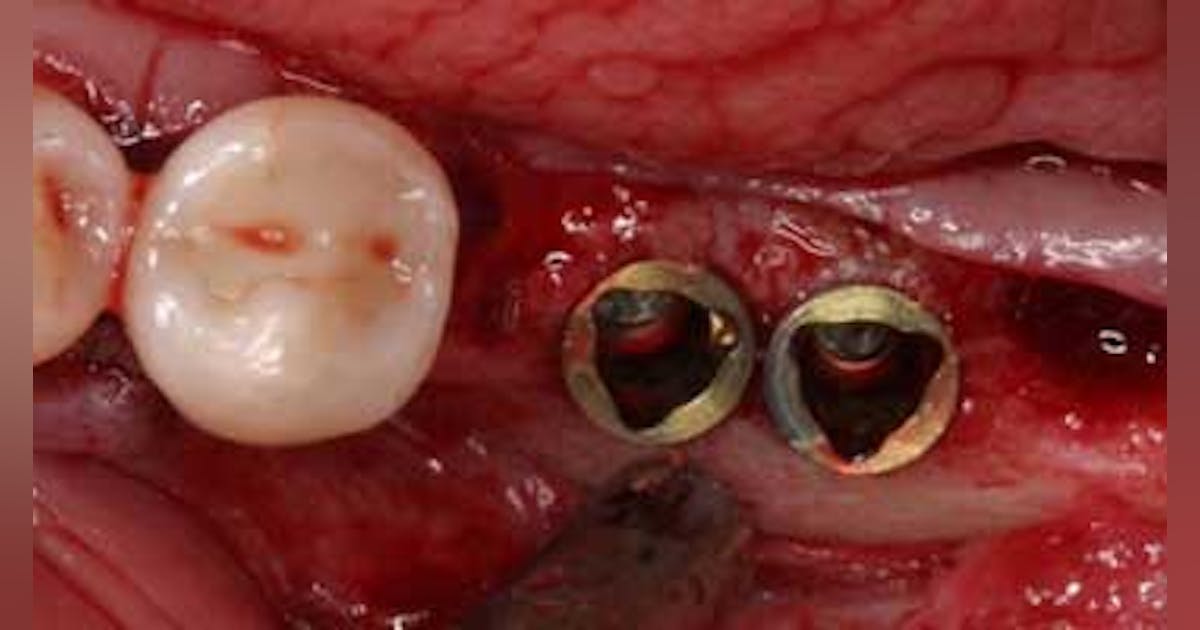

למרבה המזל, כיום ובשנים האחרונות נמצא הפתרון הטוב ביותר כדי לטפל בבעיה ומדובר בהשתלות של שיניים. הפתרון הוא החדרת שתלים דנטליים כאשר ממלאים אחרי פרוטוקול מדעי המיועד לצורת העבודה של ההשתלה, ולאחר מכן את העמסה של הכתרים אשר מתפקדים מבחינת סגר ומנשך, וכך משיגים כיום את הטיפול היותר צפוי, בטוח, אסתטי ותפקודי בין אם מרכיבים שן בודדת או מספר שיניים במקום השיניים הטבעיות.

השתלות שיניים הפכו לחלופה יוצאת מן הכלל לשיניים תותבות, בגלל שהן קטנות וממוקמות על הלסת העליונה והתחתונה ומתפקדות בצורת שורש שן ועוזרות ״להצלת הפה״ משיניים אבודות (השתלות שיניים). היתרונות של השתלות השיניים הם רבים ואפשר למנותם: השתלים הדנטליים נראים כמו שיניים טבעיות ורגילות לכל דבר. השתלים מעניקים תמיכה ויציבות מצויינת בפה בשעת הלעיסה.

השתלים דורשים השקעה לא קטנה של ממון בהשוואה למערכת שיניים להסרה או ביחס לגשר קבוע קונבנציונאלי. משך העבודה של התקנת השתלים והכתרים מעליהם נמשך זמן רב יותר ומוערך ככפול לעומת פתרונות קונבנציונאליים מקבילים אחרים. שתלי השיניים נדרשים לכירורגיה זעירה כדי להחדיר את השתל, לכן יש להישמר מדלקות, במיוחד אצל אנשים אשר מעשנים.